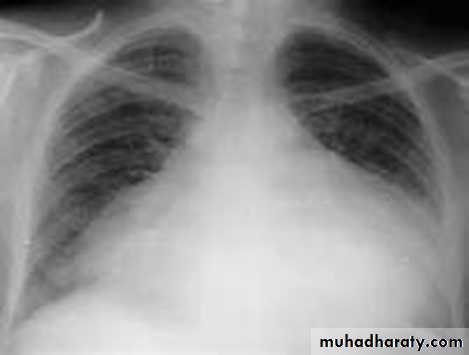

Slide1 Severe chest trauma by car accident1- What does the x ray show?2- What make the neck veins distended